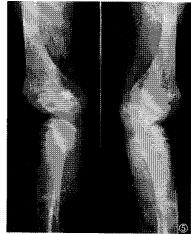

3.其他表現還可以出現腎性糖尿,胺基酸尿尿酸尿等近端腎小管功能障礙的表現。由於鈣從尿中大量丟失體內長期呈負鈣平衡少數病人可繼發甲狀旁腺功能亢進患者可發生關節痛骨質疏鬆骨折畸形和維生素D缺乏病,少數病人表現身材矮小體重不增肌無力等。

併發症:常並發尿路感染,尿路結石,繼發性甲狀旁腺功能亢進,營養障礙骨質疏鬆、骨折、畸形身材矮小、體重不增、肌無力等。